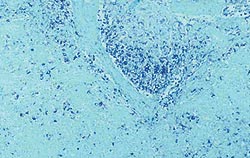

| Allure normale | Légère perturbation de l’architecture folliculaire |

| Perturbation modérée de l’architecture folliculaire | Perturbation intense de l’architecture folliculaire |

Déplétion lymphocytaire et infiltration granulomateuse légères, modérées et intenses comparées à un ganglion de structure histologique normale. Les lésions modérées et intenses sont indicatrices de la MAP. Coloration HE.